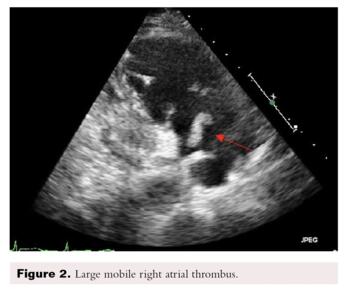

A PE protocol computed tomography angiography revealed inversion of the ventricular ratio with straightening of the interventricular septum compatible with right ventricle strain. Pulmonary emboli extending into the right and left pulmonary arteries with partially occluded filling defects extending into all lobes (Figure 4).